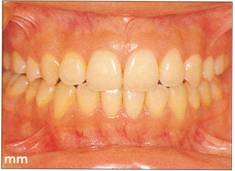

Fi 545e45f gs 5-8kk to Fi 545e45f g 5-8nn Two years 6 months after transplantation. |

|

Fi 545e45f g 5-800 Two years 6 months after transplantation. Normal appearance of periodontal ligament and lamina dura is observed. |

Fi 545e45f g 5.8pp Fi 545e45f ve years after transplantation. |